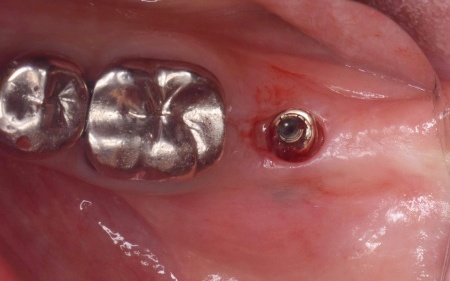

治療中

インプラント体と骨の結合を確認しました。